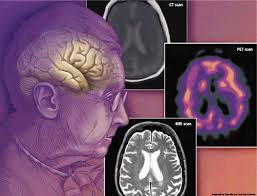

Ada banyak alasan mengapa perilaku seseorang bisa berubah. Demensia adalah hasil dari perubahan fisik di otak, dan ini dapat mempengaruhi seseorang memori, suasana hati dan perilaku. Kadang-kadang, perilaku mungkin berhubungan dengan perubahan ini, tapi di lain waktu, perilaku tersebut dapat dipicu oleh perubahan seseorang lingkungan, kesehatan atau pengobatan.